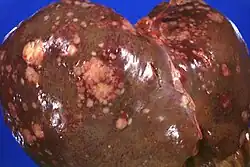

Die ersten Metastasen finden sich in den benachbarten Lymphknoten und – über den Blutstrom der Pfortader – in der Leber. Tumoren im Pankreaskörper und Pankreasschwanz sind bei Diagnosestellung zumeist größer als Pankreaskopftumoren und haben meistens schon zu Lebermetastasen oder einer Infiltration des Bauchfells (Peritonealkarzinose) geführt.